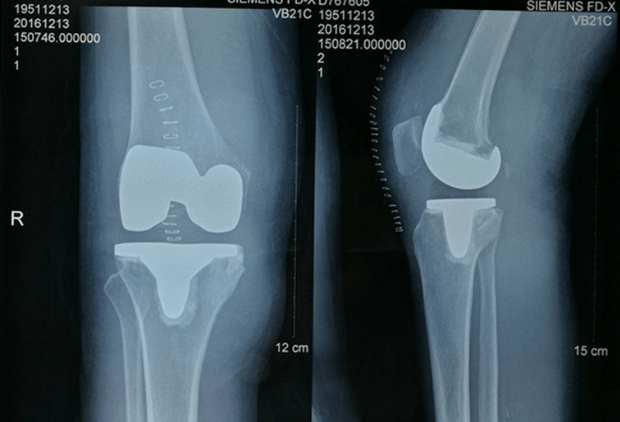

基层医院进行的一例膝关节置换,请大家指点

广东省中医院93岁患者经膝关节置换术后,4小时就能下地行走

昆明骨科医院 膝关节置换术,患者行走不再难